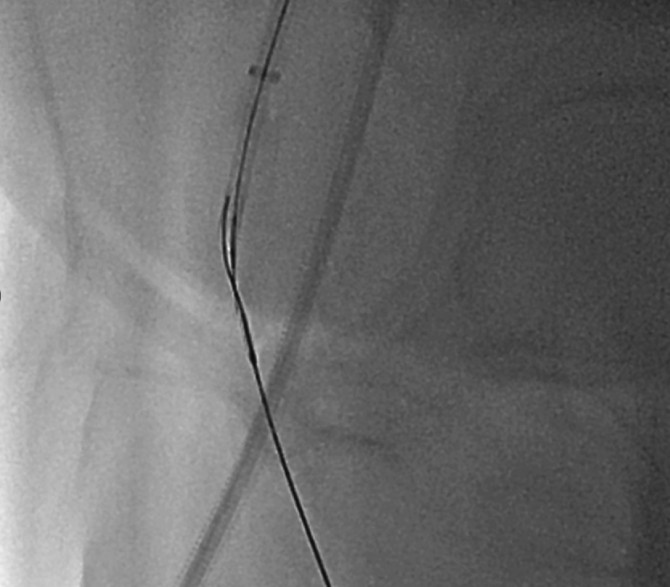

Procedural Step

An antegrade approach was first attempted via left femoral access using an 8 Fr long sheath advanced to the right femoral artery. Despite multiple manipulations, the wire and microcatheter failed to cross the calcified lesion at the superficial femoral artery ostium. The wire could engage the plaque but was unable to advance through the dense calcium. A retrograde approach was then established by puncturing the proximal superficial femoral artery under ultrasound guidance. The connection between the retrograde and antegrade wires was confirmed under orthogonal fluoroscopy. Using a rendezvous technique, the retrograde wire was advanced into the antegrade guiding catheter and externalized through the contralateral sheath, creating a continuous guidewire pathway.After wire externalization, sequential intraplaque and extraplaque rotational atherectomy were performed to modify both deep and superficial calcium. This ablation provided effective vessel preparation using a small burr size, improving compliance while minimizing procedural risk. Intravascular lithotripsy was subsequently performed to further optimize vessel expansion.Final high-pressure dilation achieved full luminal gain, followed by drug-coated balloon angioplasty as the definitive therapy. The final angiogram demonstrated excellent vessel expansion, preserved bifurcation flow, and no evidence of dissection, perforation.